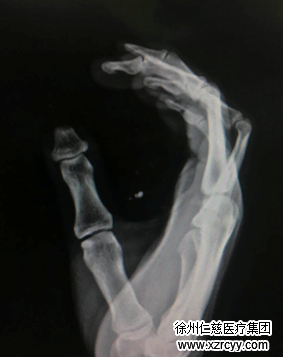

下午2点左右,车辆载着王师傅抵达必威官方首页官网betway,接诊的医生检查了王师傅的伤口后,发现患者伤情非常严重,右拇指离断指体毁损不成形,已无再植条件。

“医生,您可一定得帮我保住手指,我还要干活养家,不能没有拇指啊!”“放心,我们再想想办法,一定尽力。”医生告诉王先生,在损伤如此严重的情况下,唯一的办法就是等创面稳定后,用脚趾再造拇指。

手外科二病区黎章灿医生说,相比较于其他身体器官,手是人的“第二眼睛”,这说明手指感觉的重要意义。而拇指占手部功能的50%,如果要尽量保证拇指的长度和功能,只有从脚上取一截带趾甲、带骨头、带血管的脚趾移植到拇指上,才能达到这一要求。

“这个手术的难度在于,从脚上取下来的那截趾头要和拇指的血管相吻合,要在放大二十倍的显微镜下,用比头发丝还细的线,把极细的血管吻合缝好并保证畅通。当然,手术有一定的风险,但我们医院的拇指再造技术已经非常成熟,对患者还是有保障的。”